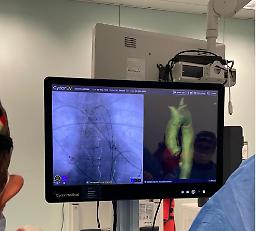

Policlinico di Palermo, eseguiti tre interventi di riparazione di aneurisma dell’aorta con l'intelligenza artificiale

Nell’Unità operativa complessa di Chirurgia vascolare del Policlinico ...